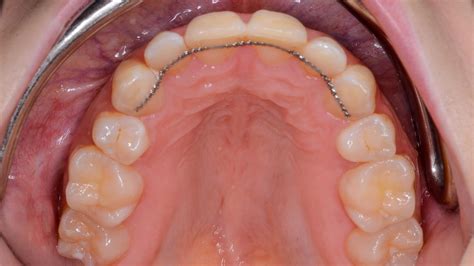

Los retenedores fijos, también conocidos como retenedores linguales o permanentes, son pequeños alambres que se colocan en la parte posterior de los dientes para mantenerlos en su lugar. Están compuestos de un alambre de metal que se coloca detrás de los dientes de la arcada superior e inferior y va de canino a canino. Este tipo de retenedor se ajusta a los dientes de forma permanente, lo que significa que no se puede retirar.

Normalmente el ortodoncista coloca este tipo de retenedores dentales el mismo día que se retiran los aparatos de ortodoncia, asegurando así mantener el posicionamiento dental. Se trata de un sistema de retención muy estético ya que, al estar colocado en la cara lingual de los dientes, es totalmente invisible externamente.

- Invisibilidad: Una de las mayores ventajas de los retenedores fijos linguales es su invisibilidad. Dado que se colocan en la parte posterior de los dientes, no son visibles cuando hablas o sonríes.